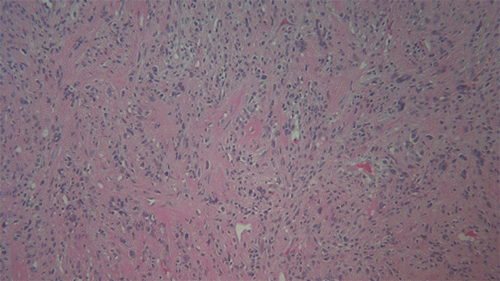

The patient underwent a mammogram-localized right breast lumpectomy and sentinel lymph node biopsy with an uncomplicated postoperative course. The excised mass was firm, tan/white, measuring 5.0 × 4.0 × 2.5 cm in size, with pathology revealing sheets of spindle cells with a Ki-67 index of 40%, consistent with high-grade sarcoma (Figure 3). The margins were tumor-free, and the lymph nodes were negative for malignancy. Immunohistochemical (IHC) stains were positive for smooth muscle actin and vimentin (Figure 4 and Figure 5, respectively) and negative for pan-keratin, S-100, p63, mammaglobin, E-cadherin, calponin, and CK 5/6. The final pathology review determined the mass to be consistent with the metastatic spread from her previous lower extremity sarcoma. The patient agreed to undergo adjuvant whole breast irradiation, followed by adjuvant chemotherapy.

Figure 4. H & E Stain of Tumor Cells Showing Sheets of Spindle Cells. Published with Permission

A. 10x magnification

B. 40x magnification